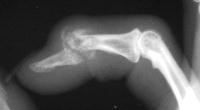

Distal interphalangeal erosive osteoarthritis severe enough that the diagnosis of giant cell or other tumor was suspected. Fortunately, no tumor was encountered at surgery.